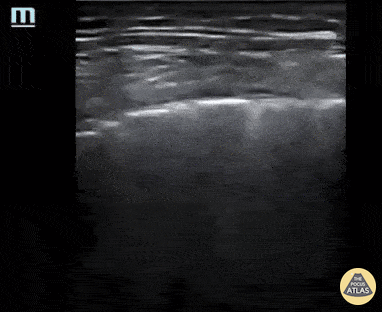

Patient presented with a 2-day history of worsening dyspnea and increased work of breathing. He was profoundly hypoxic at time of arrival with EMS (O2 sat 42% on 2L O2; improved to 75% upon being placed on high flow O2 @ 40 L/min). A linear probe was used to perform lung US and pictured here is zone L6 (posterior lower) that revealed thickened and irregular pleura in addition to B-lines. Findings were suggestive of clinically-suspected COVID-19 pneumonitis. Cian McDermott, Emergency Physician Dublin, Ireland @cianmcdermott